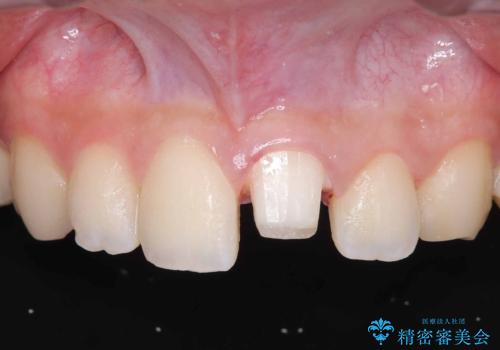

- 歯冠破折により点状露髄を認めました。破折から1週間以内であったこと、また歯髄診断により生活反応が良好で保存可能と判断したため、VPT(生活歯髄療法)を行い神経の保存を試みました。

- 税込209,000円(VPT歯髄保存療法44,000円+仮歯11,000円+オールセラミッククランスペシャル154,000円)費用は治療当時の料金となります